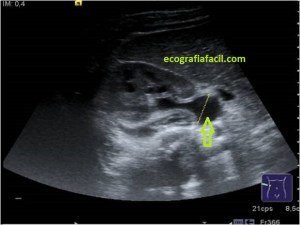

En la imagen 3 ves una imagen de un lipoma, mide 7 cms, la huella de la sonda mide 5cms, la «panoramic view» posee una regla centimetrada que sigue el contorno de la imagen, justo en la profundidad de la misma y lo marca la flecha amarilla. La profundidad la marca la flecha roja y la flecha blanca marca el rango centimetral de los 5cms, fíjate que la línea blanca es ligeramente mayor cada 5 cms. Sirve de referencia, como en la imagen 4 donde ves una colección en el glúteo de más de 10 cms.